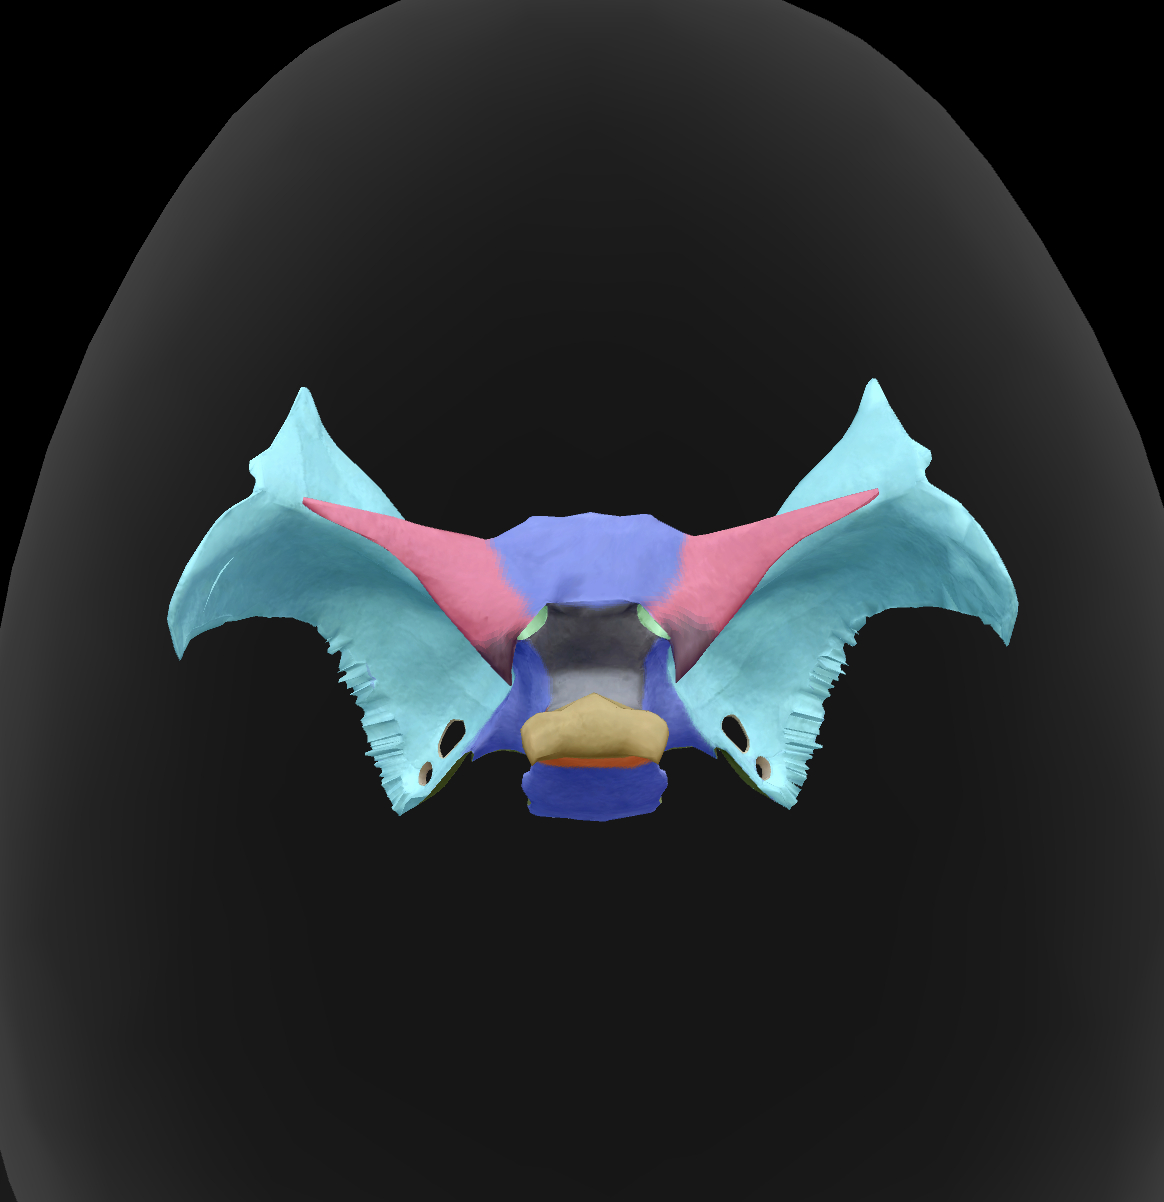

What is the name of this bone?

sphenoid bone

body

What is the name of this feature?

lesser wings

What is the name of this feature?

sella turcica

What is the name of this feature?

greater wings

What is the name of this feature? (the hole)

optic foramen

What is the name of this feature?

lateral pterygoid plate

What is the name of this feature?

medial pterygoid plate

What is the name of this feature?

superior orbital fissure